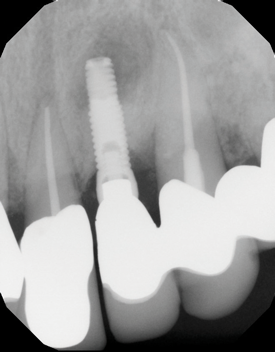

(12.) Immediate postoperative digital radiograph demonstrating the graft material in place.

Figure 12

In this case, the procedure was precise, and the patient experienced minimal postoperative discomfort. An immediate postoperative digital radiograph was acquired to evaluate the radiolucent appearance of the grafted apical defect (Figure 12). After 8 weeks, the tissue appeared to be healing quickly and predictably (Figure 13), and a follow-up sagittal CBCT analysis demonstrated a new wall forming where the dehiscence had been present (Figure 14). The patient was recalled again after 5 months for radiographic analysis and intraoral evaluation, which revealed that the healing was progressing without complication (Figure 15 through Figure 18).